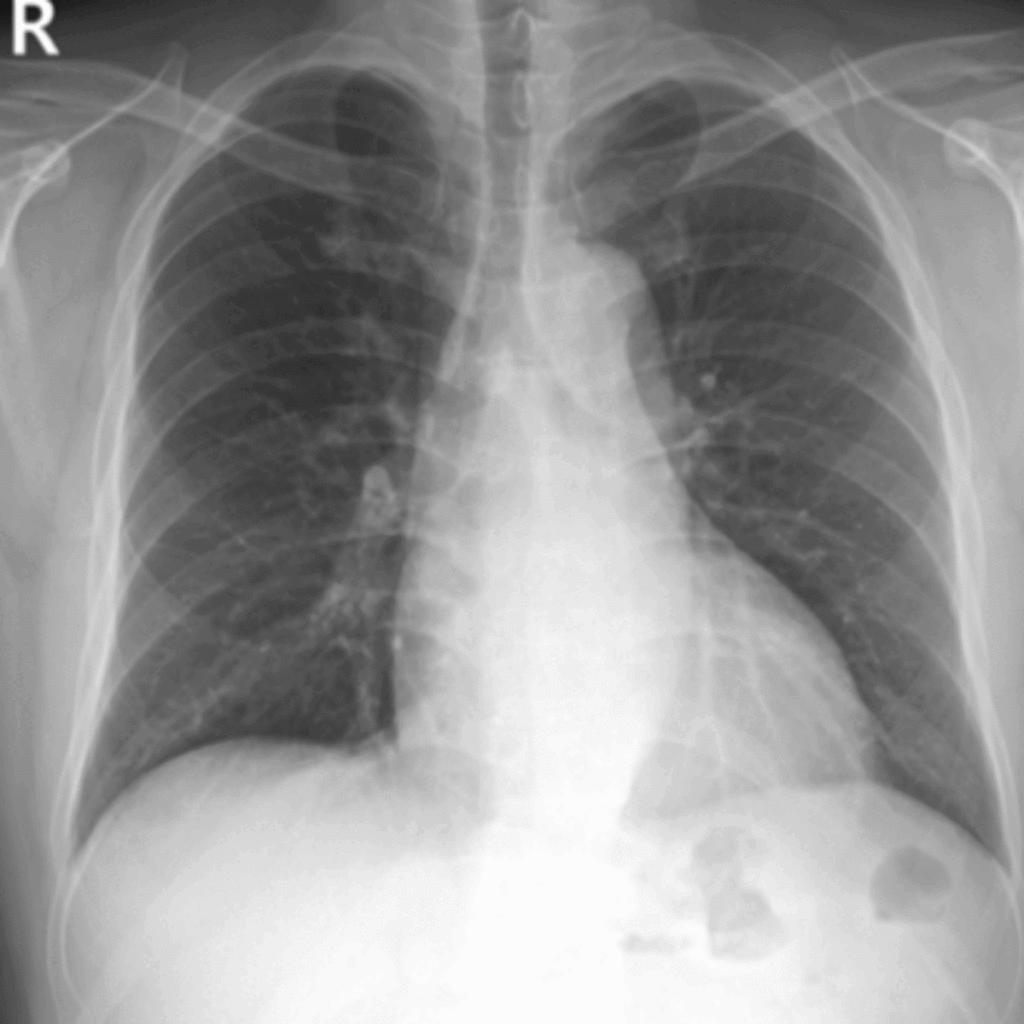

오랫동안 고혈압을 가지고 계셨지만 관리하지 않으셔서 심부전(심장기능저하)가 나타난 환자분 심장초음파 결과

고혈압 환자분의 경동맥 초음파 결과